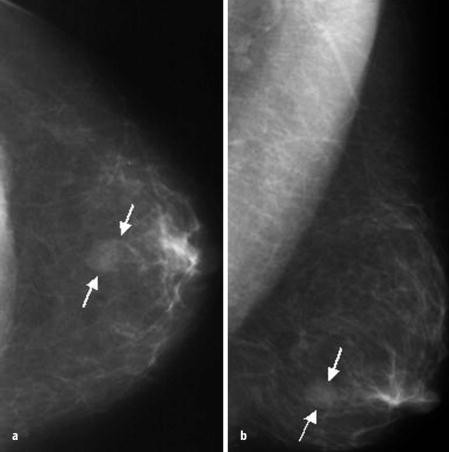

Verkalkungen Abb 260 Typisch benigne Rund Diffus verstreute runde (punktförmige) und typisch benigne Verkalkungen. Verkalkungen in der Brust können durch verschiedenste Gründe entstehen und sind nicht direkt Grund zur Sorge Es können sowohl gutartige Verkalkungen sein, wie eine einfache Zyste oder ein Fibroadenom, als auch leider bösartige Verkalkungen, die auf Brustkrebs hindeuten Daher ist es wichtig so eine Verkalkung beim Arzt abklären zu lassen, sodass falls nötig direkt mit einer Therapie. Kleine Verkalkungen in der Brust, die als gutartig beurteilt wurden, werden zur Sicherheit im jährlichen Abstand erneut untersucht Gefährliche Verkalkungen Dass eine Verkalkung in der Brust besteht, heißt also nicht zwangsläufig, dass eine bösartige Erkrankung zugrunde liegt.

Diagnose Kalk in der Brust Kalkschatten in der Brust fallen meist bei Vorsorgeuntersuchungen mittels Ultraschall oder häufiger in der Mammographie (Röntgenuntersuchung der Brust) auf Sie gehen selten mit Beschwerden einher Die Kalkschatten oder Mikrokalzifikationen kommen in verschiedenen Größen und entweder allein oder in Gruppen vor. Solche Verkalkungen verursacht durch Verletzungen erscheinen gekrümmt oder asymmetrische Form Brustkrebs Verkalkungen zu einem Thema für eine Frau, wenn Clustering gefunden wird Auch ist ein weiteres weit verbreitetes Missverständnis, dass eine Biopsie an der Brust Verkalkungen kann nur chirurgisch durchgeführt werden. Benigne Verkalkungen Ähnliche Verkalkungen waren auch andernorts in der gleichen Mamma und in der anderen Brust vorhanden Man beachte die ebenfalls typische benigne Gefäßverkalkung im unteren Bildanteil 47 22 .